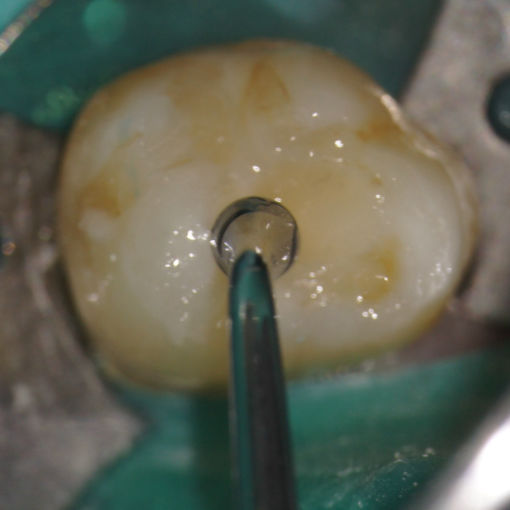

Si experimenta alguno de estos síntomas, su dentista probablemente le recomendará un tratamiento no quirúrgico para eliminar la pulpa enferma. Esta pulpa lesionada se retira y el sistema de conducto radicular se limpia y sella completamente. La terapia del conducto radicular generalmente involucra anestesia local y puede completarse en una o más visitas, dependiendo del tratamiento requerido. El éxito de este tipo de tratamiento ocurre en aproximadamente el 90% de los casos. Si su diente no es susceptible al tratamiento de endodoncia o la posibilidad de éxito es desfavorable, se le informará en el momento de la consulta o cuando se presente una complicación durante o después del tratamiento.

Una vez que se ha seleccionado el retratamiento como una solución a su problema, retrataremos su diente para tener acceso al material de relleno del conducto radicular. Este material restaurador se eliminará para permitir el acceso al conducto radicular y limpiar y examinarar cuidadosamente el interior del diente problemático. Una vez limpios, los conductos se rellenarán y sellarán.